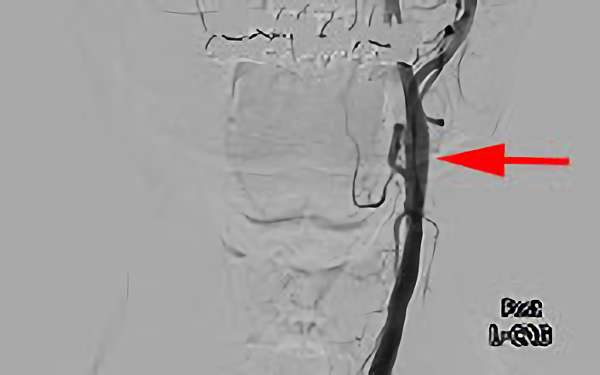

右内頚動脈狭窄症

70代

院内外来

No.475 手術前

No.475 手術中

No.475 手術後